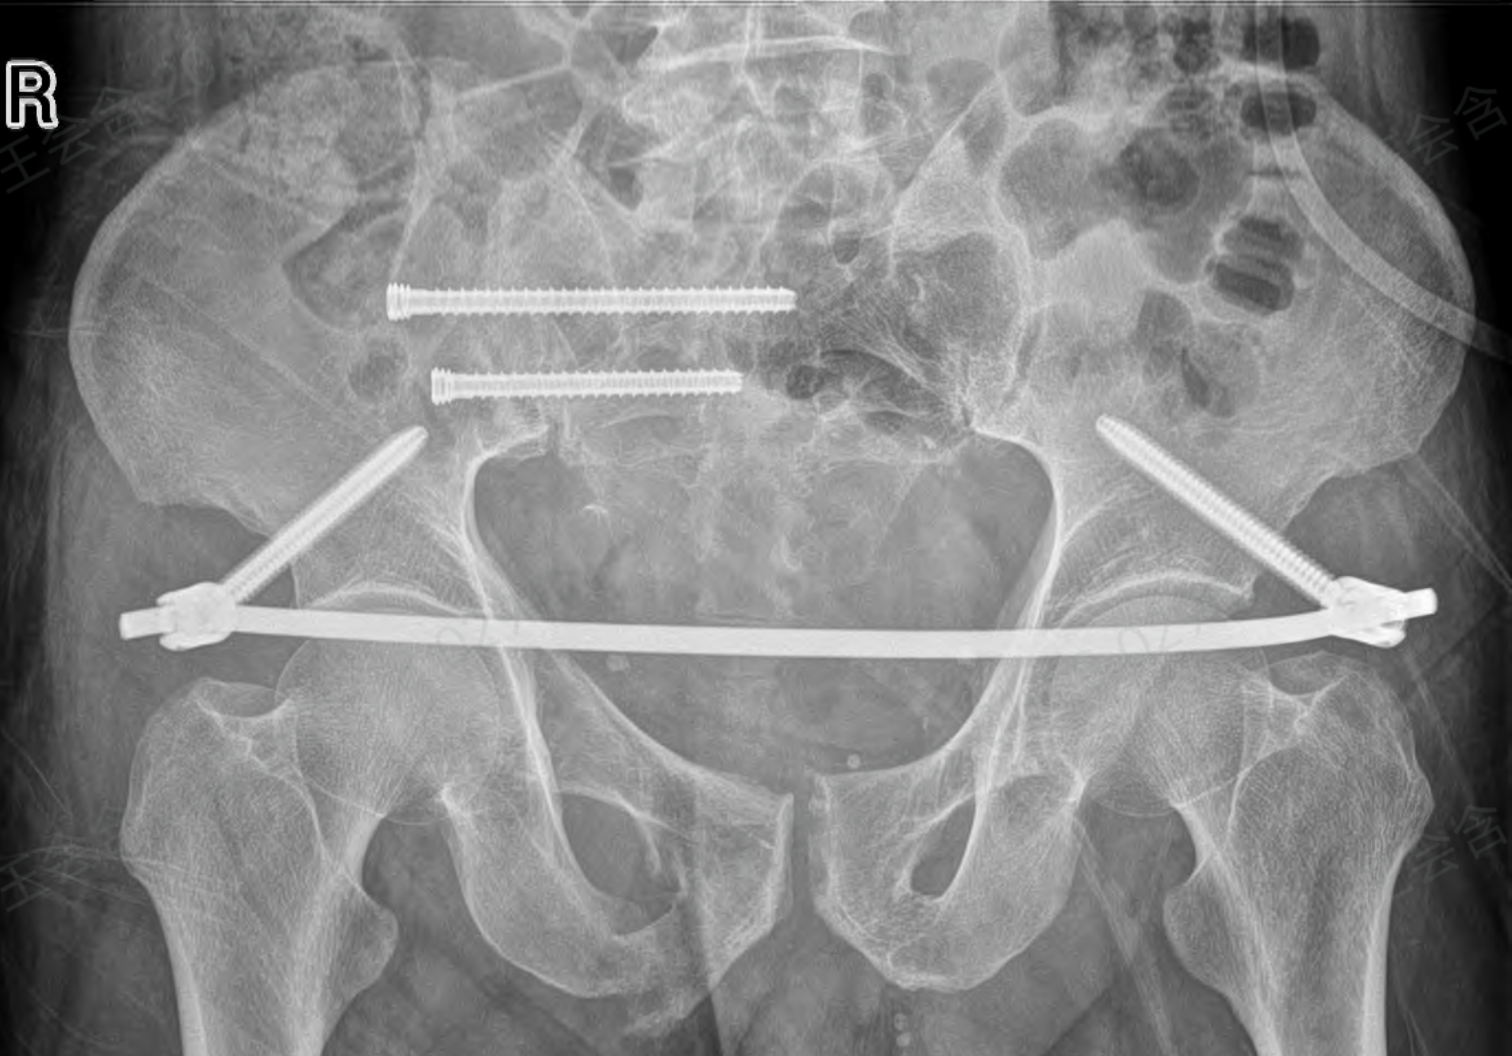

针对患者高危病情,骨科团队迅速联合麻醉科、ICU启动多学科协作(MDT)会诊,最终确定采用“天玑机器人辅助下闭合复位骶髂关节空心螺钉内固定术+前环infi固定术”的个性化方案,依托智能导航优势破解传统手术“定位难、创伤大”的痛点。

术中,机器人机械臂在光学追踪系统引导下自动调整至预设位置,亚毫米级定位精度可实时修正手术偏差,避免人为操作误差。医生仅通过4个1cm左右的微小切口,经皮置入导针、空心螺钉和infix螺钉,便完成了骨折端的稳定固定。

整个过程无需广泛剥离软组织,术中出血量较传统开放手术减少90%以上,且医护人员无需暴露在X射线辐射区域,实现了医患双重安全保障。术后影像学检查显示,骨折复位优良,螺钉位置完全符合术前规划,未出现任何血管神经损伤并发症。